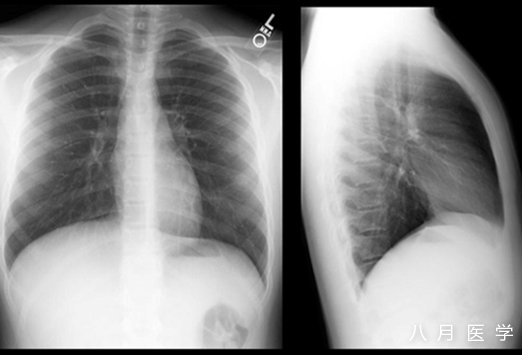

胸片如图4,可见何种异常?

图4

A. 符合肺炎表现

B. 充血性心衰表现

C. 正常胸片

D. 纵隔增宽,可能存在主动脉夹层

答案:C